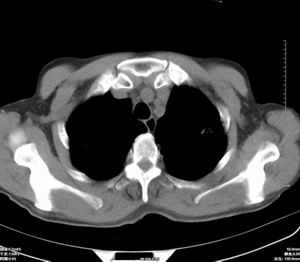

男 60岁,咳嗽,胸疼半年,请各位老师讨论.

肺内多发小结节,部分内见空泡,边界大部分清楚.多考虑:1 韦格氏肉芽肿.2 肺泡癌伴肺内转移不除外.

肺内多发结节样病灶,部分内见空泡影,边界大部分清楚,多考虑:

1.金葡菌感染

2 转移不除外

影像学表现:文献报告肺部浸润性见于50-65%的病人,肺部均有浸润,表现为肺内多发或单发结节影,出现多发厚壁空洞,内壁粗糙,易合并细菌性肺炎,也可出现胸腔积液。ct及hrct扫描可见大小不等的结节多分布于肺周边部,结节可呈楔形贴近胸膜,另一主要特征是其周围有线状斑痕影,即长毛刺征,受累血管及血管周围纤维化是其形成的原因,如累及胸膜尚可出现胸膜凹陷征。71%ct比胸片发现更多更小病灶, 典型的征象滋养血管征仅能在ct上显示。ct及hrct可检出典型影像征象。为诊断提供了重要依据,ct可成为肺韦格氏肉芽肿首选检查方法。

鉴别诊断:韦格氏肉芽肿ct表现与肺有关病变相似。如脓毒性肺栓塞的ct表现包括多发性,并有滋养血管的空洞性结节。滋养血管征也常见于肺梗塞和血行转移瘤。另外部灶呈楔形贴附胸膜面也是梗塞和脓毒性肺栓塞的ct特点之一。但肺梗塞和脓毒性肺梗塞的临床表现较急、全身或局部症状明显,另外肺结节边缘长毛刺征及胸膜凹陷征是上述病变所缺乏的,有助于本病的诊断和鉴别诊断。所以本病例应考虑肺转移。